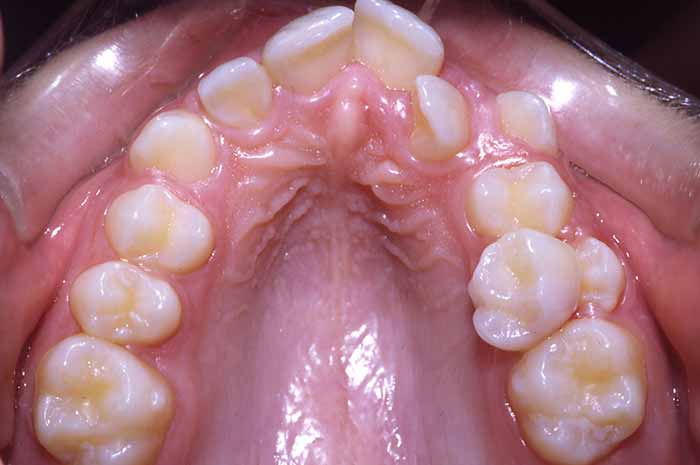

Tratamiento realizado:

Ortodoncia convencional con brackets metálicos

En este caso, para conseguir un resultado óptimo, también se utilizó un aparato removible (de quita y pon) en la arcada superior, previo a la colocación del aparato fijo (brackets).

La excepcional colaboración de la paciente fue fundamental para la consecución de los resultados.

Antes y Después